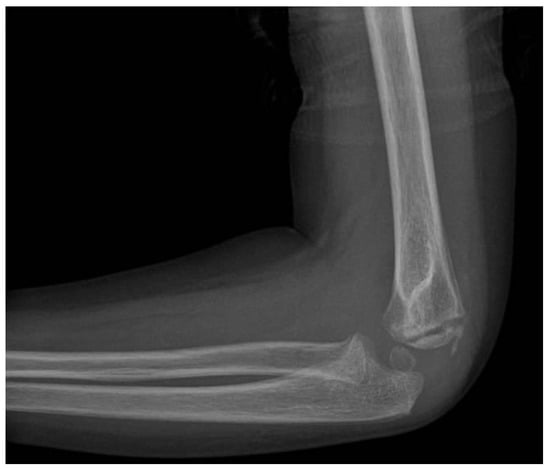

Lateral Humeral Condyle Fracture in Childhood: Results of a New Surgical Technique